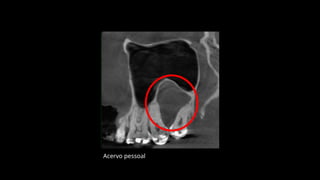

CASO CLÍNICO

Acervo pessoal

Os ceratocistos odontogênicosexibem uma área radio lúcida, com margens escleróticas frequentemente bem definidas. Lesões grandes, particularmente no corpo posterior e no ramo da mandíbula, podem se apresentar multiloculadas.